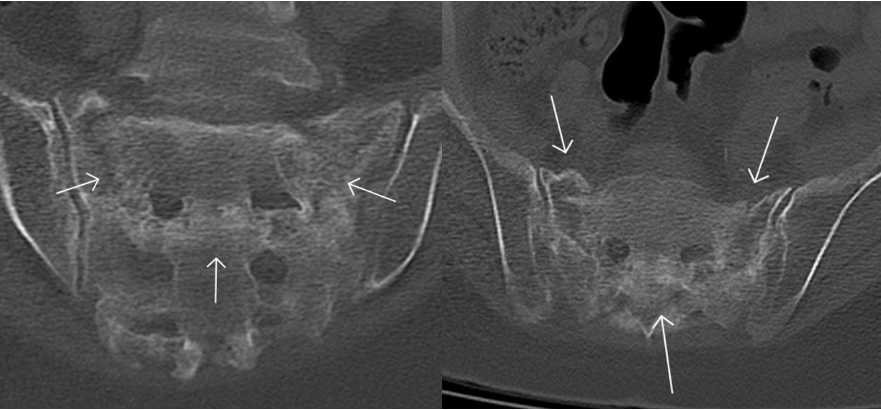

骶骨机能不全骨折 CT 表现

骨质疏松、骨质密度减低,骨皮质或骨小梁断裂,可见骨折线显示,骨折线位于骶孔外侧,平行于骶髂关节,多为双侧,也可为单侧,冠状位显示「H」征,骨折愈合期显示骨质硬化改变。